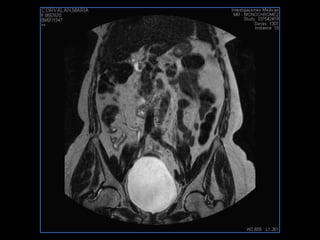

PROTOCOLO pelvis SAG T2, Y FAT SAT (FINOS) AXIAL T1  AX FAT SAT CON   GADOLINIO :  AX T1 Y COR T1 SAT: NO  FASE: RL THK: 3MM  COIL:  GAP: (FACTOR 1.4) 1MM FOV: 40 CM NEX:2 SINCRONIZACION RESPIRATORIA EN 3 O 4 CICLOS ALE